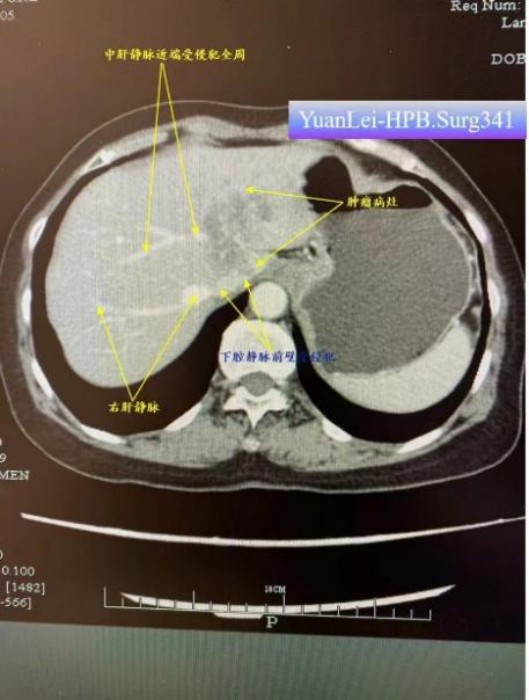

來自衢州市龍游縣68歲的藍(lán)阿姨,因腹痛去醫(yī)院檢查,診斷為左肝及尾狀葉肝內(nèi)膽管癌,侵犯中肝靜脈近端主干360度、侵犯下腔靜脈。因手術(shù)風(fēng)險(xiǎn)大,從當(dāng)?shù)蒯t(yī)院慕名轉(zhuǎn)入袁磊團(tuán)隊(duì)進(jìn)行手術(shù),袁磊組織團(tuán)隊(duì)進(jìn)行術(shù)前討論,制定了詳細(xì)的手術(shù)方案和風(fēng)險(xiǎn)防范措施,術(shù)前即擬定了全肝血流阻斷方案。術(shù)中在下腔靜脈受侵的部位處理時(shí),憑借高超的手術(shù)技術(shù)和過人膽識(shí),袁磊果斷實(shí)施全肝血流阻斷,切除受侵部分下腔靜脈前壁,從容修補(bǔ)靜脈壁缺損,成功完成了解剖性肝左三葉+全尾葉切除術(shù)+下腔靜脈壁修補(bǔ)+區(qū)域淋巴結(jié)清掃+膽囊切除術(shù)。